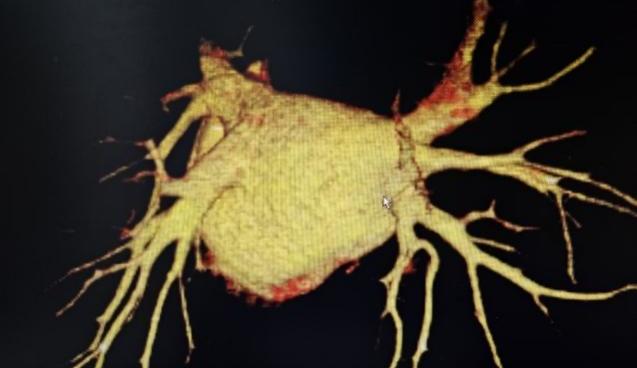

FARAPULSE导管花瓣消融